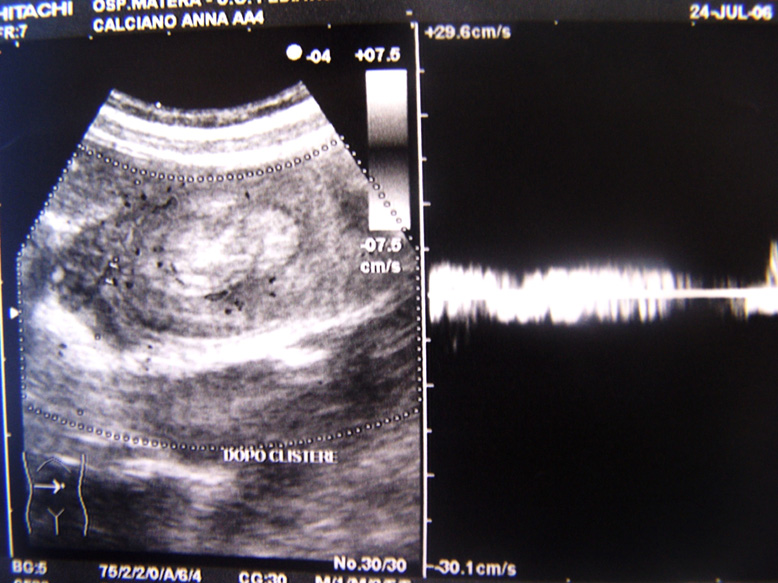

Il quadro ecografico dopo il clisma si modifica un poco (riduzione dell�asse maggiore della massa e comparsa di minima quantit� di liquido nel suo contesto) (Figura 2a). Il segnale doppler � ben apprezzabile (Figura 2b).

Figura 2 (b)Segnale doppler dopo clistere.